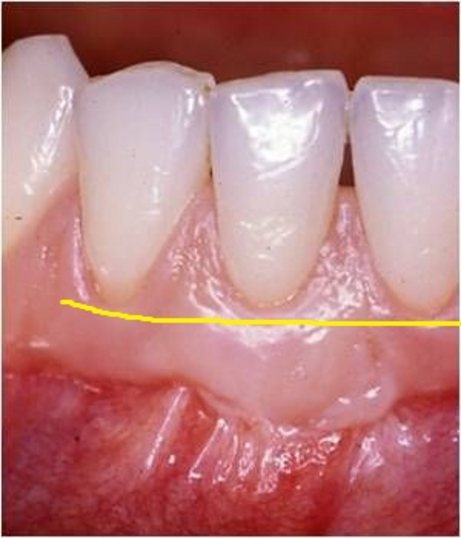

Radici dentali esposte sono il risultato della recessione gengivale. I denti in questi casi spesso sono sensibili a cibi e liquidi caldi, freddi o acidi. Le cause per cui si hanno recessioni gengivali sono le stessa da cui originano le parodontiti, prime tra tutte placca batterica, scarsa igiene orale, traumatismi, fumo. Esistono poi una varietà di fattori predisponenti che dovrebbero essere individuati per limitarne l’azione distruttiva e per prevenire l’ulteriore perdita di gengiva ed osso.

Innesti di tessuto molle possono essere utilizzati per coprire le radici esposte ma anche per ricostruire il tessuto che è andato perso. Il tessuto molle viene prelevato dal palato o da altre zone intraorali. L’intervento è quasi indolore e non esistono possibilità di rigetti. Il tessuto prelevato dalla zona donatrice si riforma spontaneamente in poche settimane.